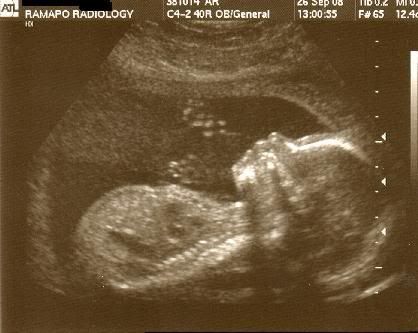

So, everything went very well with my little 's anatomy scan! He was wiggling up a storm. My Mom and Stepdad got to come in and see him too. Every organ and system is developing perfectly and he appears to be happy and healthy with 10 fingers and 10 toes! He's also measuring right on schedule.

So, without further adieu....here's my baby at almost 20 weeks (19 Weeks, 6 Days)